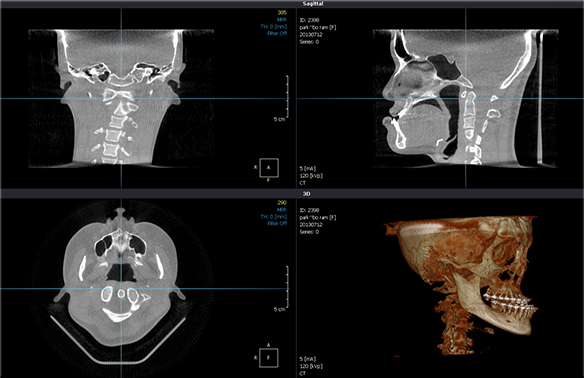

- ¾Ç±³Á¤ ¼ö¼ú½Ã CT´Â ¾î¶»°Ô »ç¿ëµÉ±î¿ä?

- ÀÔ¼úÀ̳ª »´°ú °°Àº ¿¬Á¶Á÷ÀÇ µÎ²²¿Í º¯È·®À» ÆÄ¾Ç

- ¼ö¼ú ÀüÈÄÀÇ ¾È¸ð º¯È¸¦ 3Â÷¿øÀûÀ¸·Î °Ë»ç

- ÅÎ ¾ó±¼ ºÎÀ§ÀÇ ¸Å¿ì º¹ÀâÇÑ ³»ºÎ±¸Á¶(Ç÷°ü, ½Å°æ)¸¦ ÆÄ¾Ç

- ¼ö¼ú ÀüÈÄ ±âµµÀÇ ¿ë·®À̳ª À§Ä¡¸¦ Æò°¡ÇÏ¿© º¸´Ù ¾ÈÀüÇÏ°í Æí¾ÈÇÑ ¼ö¼úÀ» ÇÒ ¼ö ÀÖ°Ô ÇÔ